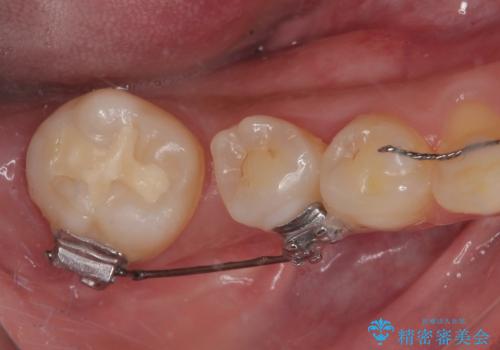

- 上顎大臼歯が食事の度に痛みを感じるとのことで来院された患者様です。

レントゲン写真などで診査を行ったところ、神経組織が壊死し、根尖部周辺の骨に炎症が認められました。

まずは根管治療を行い、症状が消退したことを確認してオールセラミッククラウンにて補綴治療を行うこととしました。

根管治療を行った奥歯は、再発防止や残された歯質を守るため、クラウンによる補綴治療が必要となります。